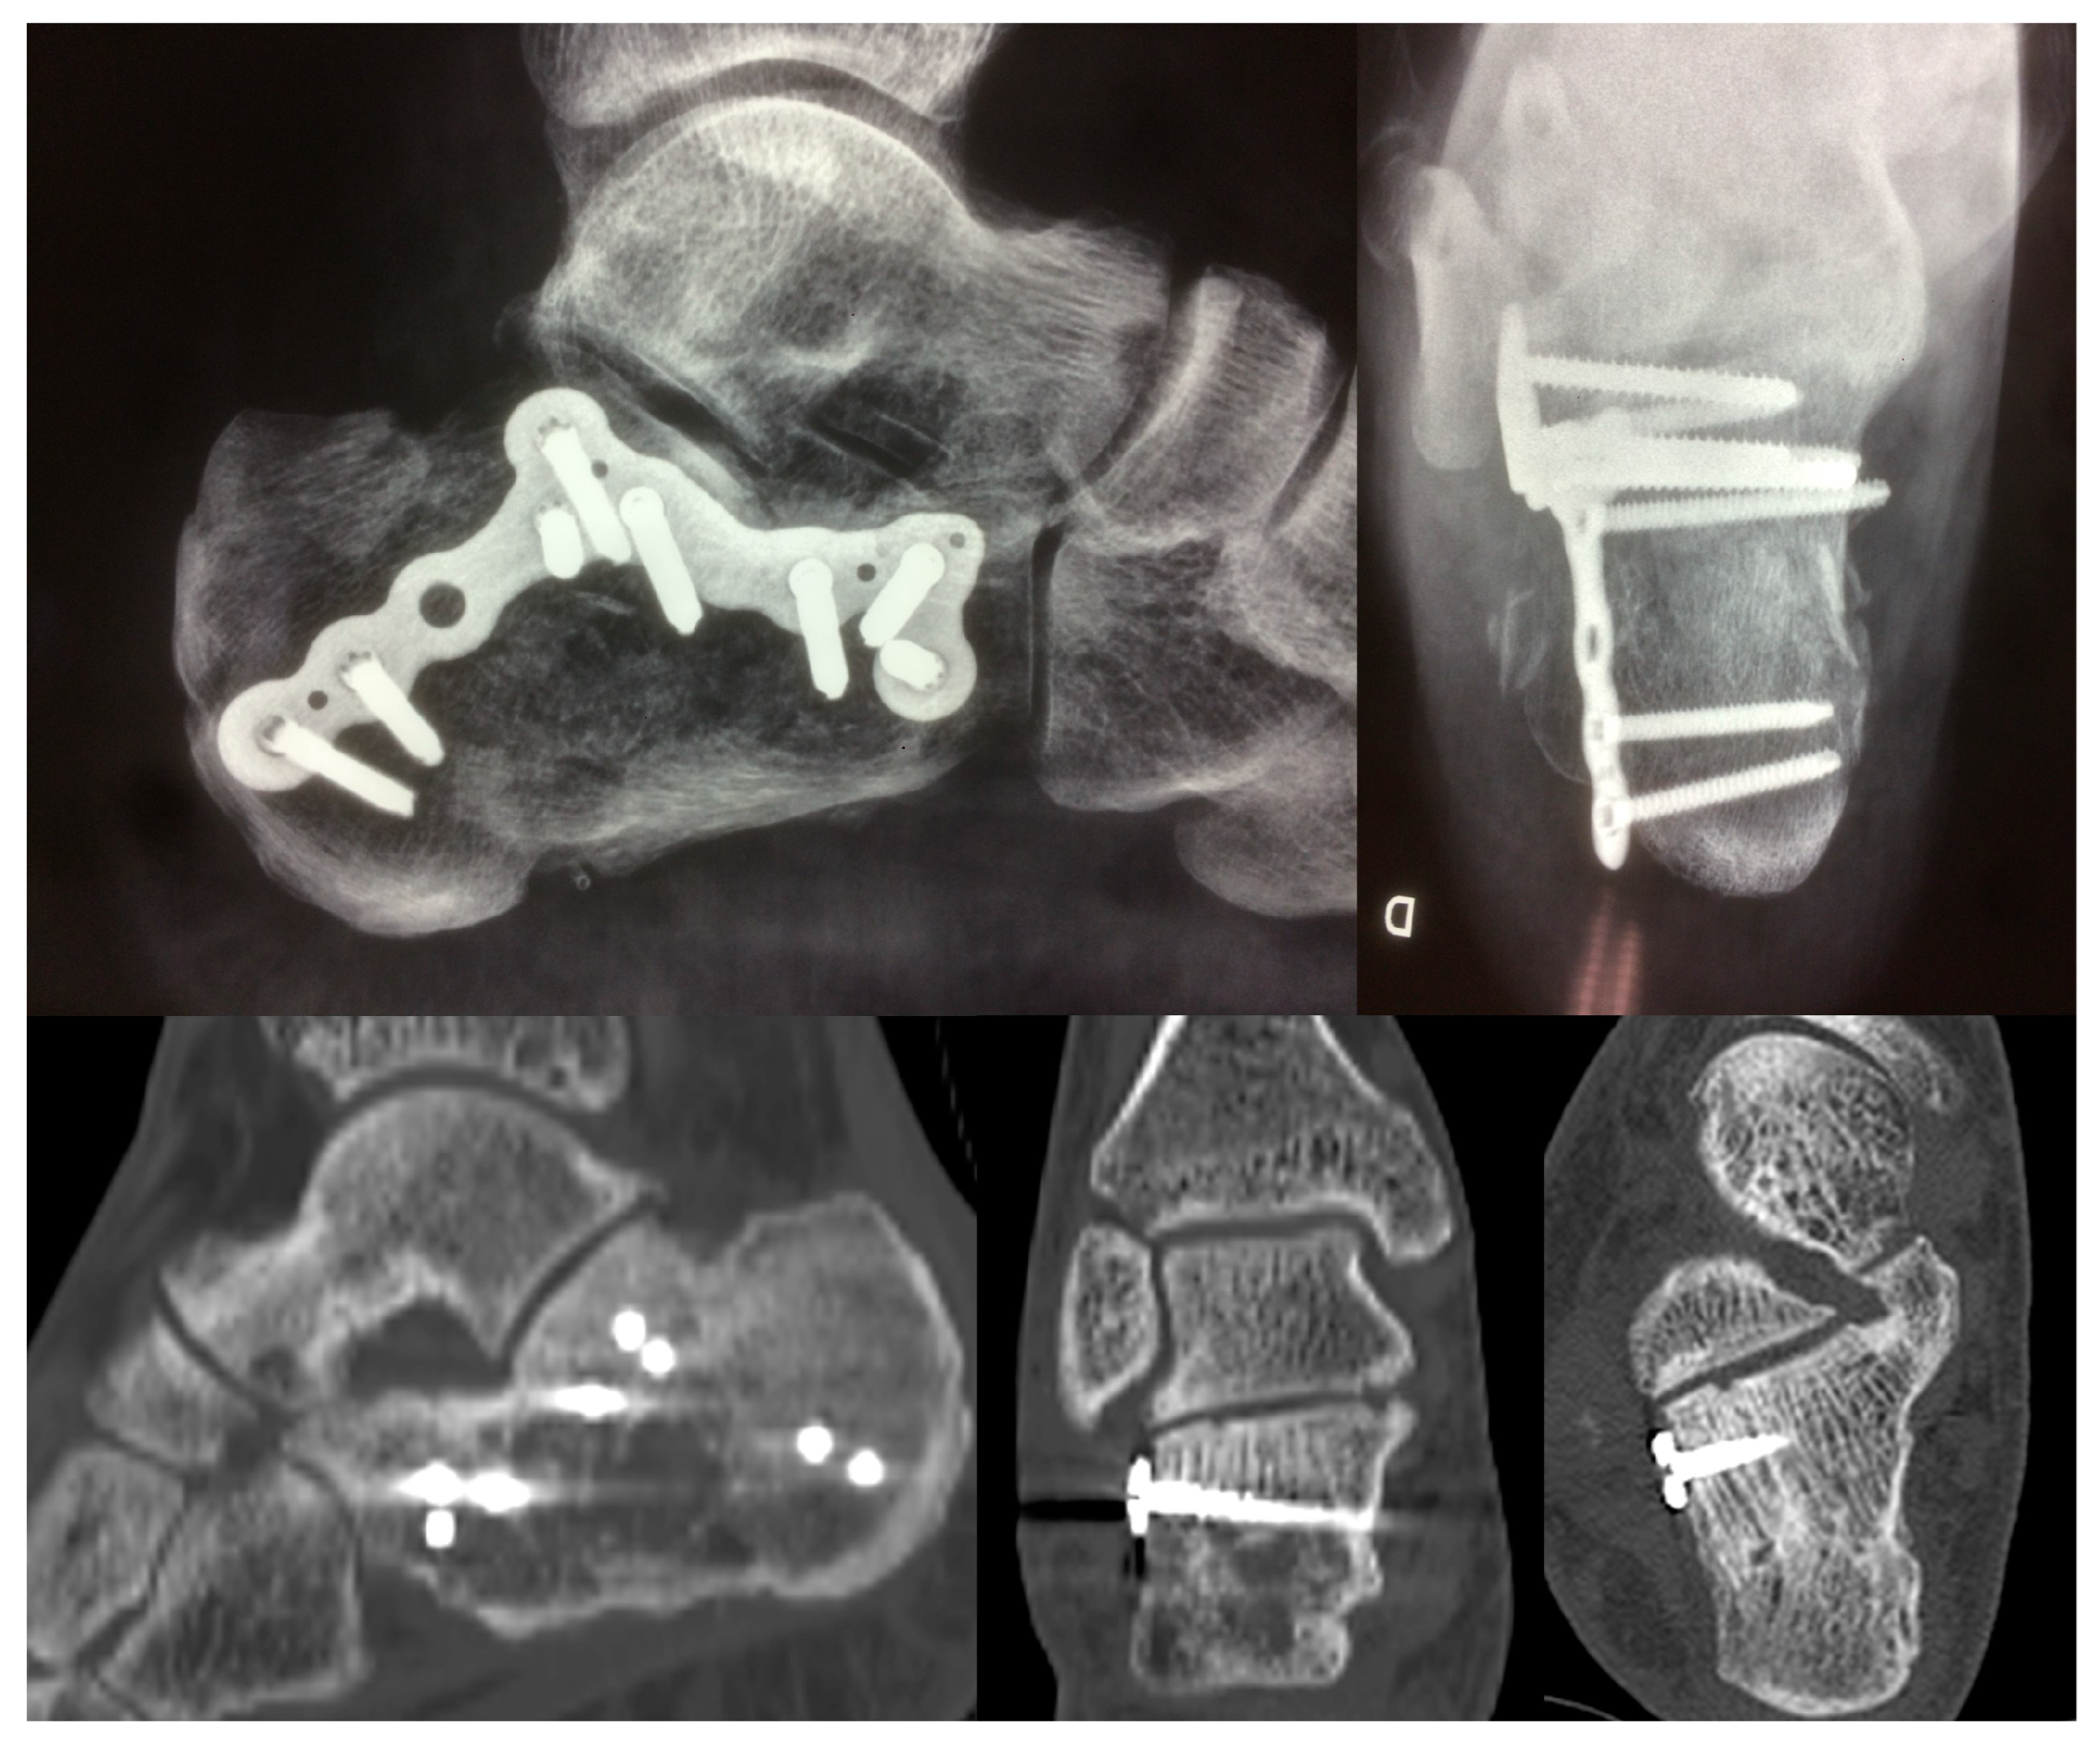

| Patient Position | Lateral Decubitus |

| Intra-operatory aids | C-arm fluoroscopy |

| Anatomical markers | Tip of the lateral malleolus Base of the 4th metatarsal bone |

| Fragments exposure | Release of the inferior peroneal retinaculum Release of the CFL and subtalar ligaments SJ exposure |

| Steps for fragments reduction | Reduction of the PT fragment to the sustentacular constant fragment Reduction of articular fragments from posterior to anterior |

| Osteosynthesis | Temporary fixation with K-wires IF with plate and screws |

| Wound Complications | |||

|---|---|---|---|

| Group A | N. 4 (34 fractures; 12%) | 3 superficial; 1 deep | p = 0.60 |

| Group B | N.2 (20 fractures; 10%) | 1 superficial; 1 deep | |

| Duration of surgery (Min) | |||

| Group A | 95.67 ± 22.93 | p < 0.001 | |

| Group B | 167.35 ± 30.93 | ||